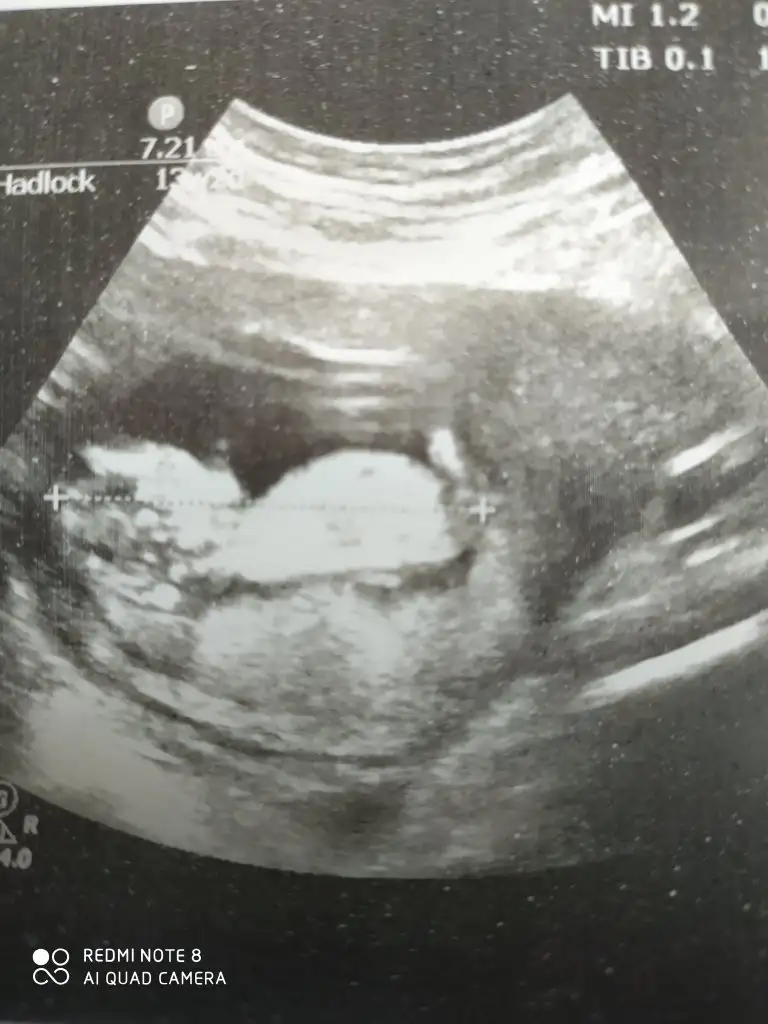

Dün öğrendim sonucu sağlıklı bir kızçe annesi olucakmışım tahminlerin için teşekkürlerUsg kaç haftalık başka usg varsa paylaşın 11 +yada 12+

Merhaba 9 haftalığızSaglıkla gelsin prensesevet tahmimde kız gibiydi

Ben de merak ediyorum ama biraz daha bekle denildi tahmininiz var mı acaba?